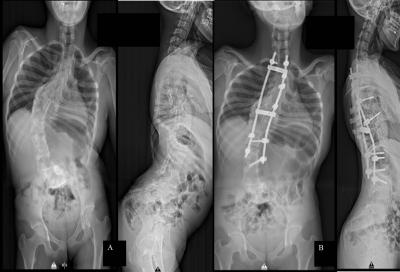

Figure 1: (A) Whole spine radiograph showing thoracolumbar curve with Cobb’s angle of 80˚, apex at T11 and failure of vertebral segmentation at multiple levels. (B) Improvement in Cobb’s angle of 56˚ with improvement in lung volume post-surgery.